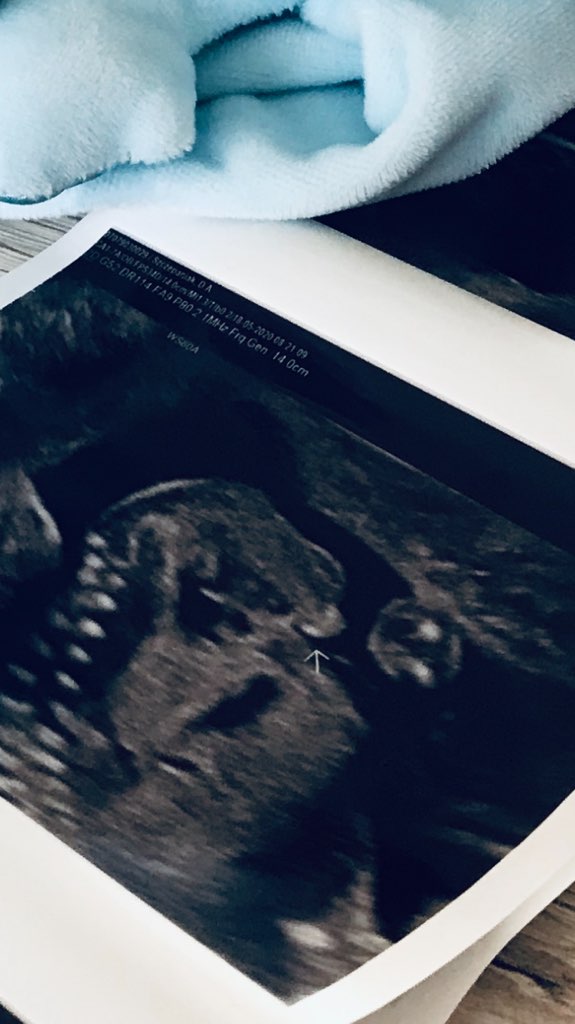

Hej, miałam parę dni temu USG połówkowe. W 12 tyg była to na 70% dziewczynka. Teraz lekarz sam nie wiedział i pytał mnie co było nakreślone. Odpowiedziałam, że 50/50. I tu nastała cisza... W końcu powiedziałam, że bardziej w kierunku dziewczynki miało iść i wtedy stwierdził "-no tak, tak dziewczynka, prawie". USG robione tylko w trybie 2D, dziecko nie chce zbytnio się pokazać, nóżki cały czas przy sobie.

Jak Dr sprawdzał kość udową, to z profilu odstawał taki "balonik" jak na zdjęciu niżej. Później dziecko znów zaczęło się wiercić, ten balonik ginął a od przodu w ogóle nie byłam w stanie zerknąć czy są te 3 kreseczki czy też nie... Niby coś tam bielszego było ale czy to na pewno 3 kreski to nie jestem pewna... Ale skoro on nie mógł tego odszyfrować to tym bardziej ja.